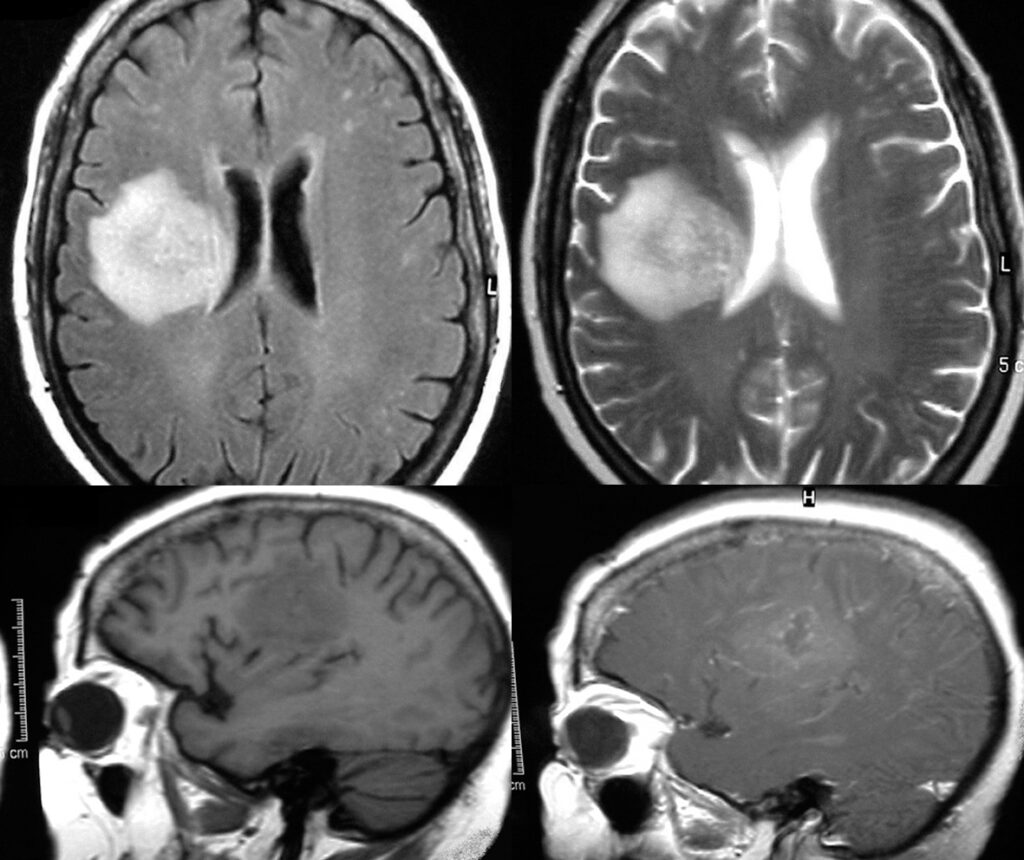

El absceso cerebral, una complicación grave y potencialmente mortal, se manifiesta como una lesión intracraneal ocupante de espacio debido a la acumulación de pus en el cerebro. Esta condición puede tener diversas causas, pero frecuentemente surge como secuela de infecciones que afectan áreas adyacentes al cráneo, como los dientes, el oído o la nariz. Esto se debe a la proximidad anatómica de estas estructuras al cerebro y a la capacidad de las bacterias o los patógenos para propagarse a través de los tejidos blandos circundantes o de la corriente sanguínea.